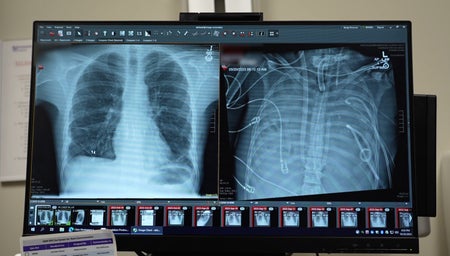

Doctors keep patient alive using ‘artificial lungs’ for two days

Novel artificial lungs could help keep people whose lungs no longer function alive long enough to get an organ transplant